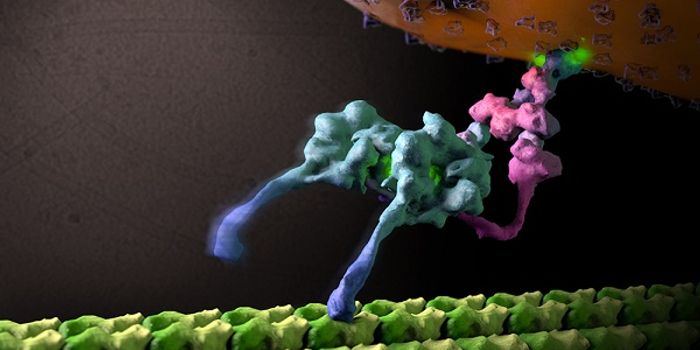

NOV 01, 2020MicrobiologySARS-CoV-2, which causes COVID-19 has to get into cells to cause infection. It does so with a spike protein on its surfa ...